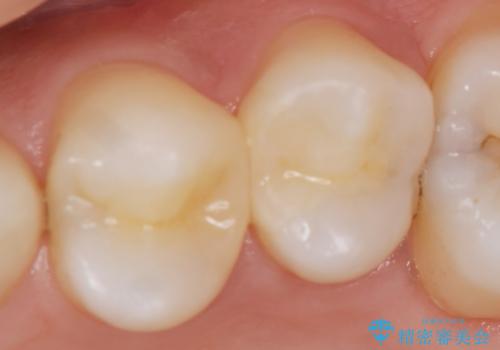

神経近くにまで及んだ大きなむし歯のセラミッククラウン